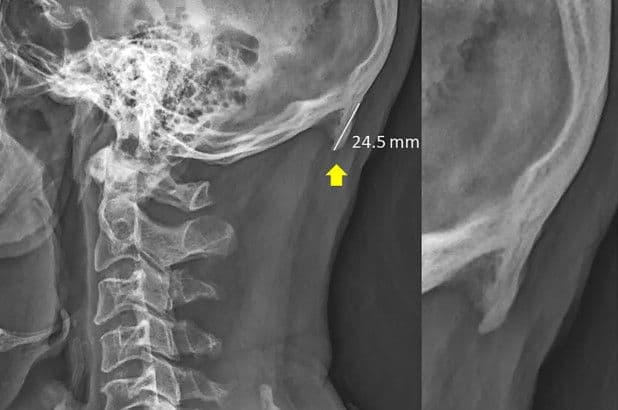

या युनिव्हर्सिटीने एक रिसर्च पेपर प्रसिद्ध केला आहे त्यात असा दावा करण्यात आला आहे, की जे मोबाईलवर तासनतास पडीक असतात. त्यातल्या त्यात ज्यांचे वय 18 ते 30 च्या दरम्यान आहे ते लोक या नविन प्रॉब्लम मध्ये अडकू शकतात. सनशाईन कोस्टच्या रिसर्सनुसार मोबाईलवर जास्त वेळ काम करणाऱ्या व्यक्तीच्या डोक्याच्या मागच्या भागात एक अणकुचीदार हाड वाढत असते. या अणकुचीदार हाडाला 'टेक्स्ट नेक' असे नाव देण्यात आले आहे. या हाडाचा आकार 2.6 सेमी पर्यंत असु शकतो. आणि हा फक्त दावा नाही मंडळी असे हजारो केसेस पुढे आलेल्या आहेत ज्यात स्पष्ट समजते की जे मोबाईलचा अतिवापर करतात त्यांच्या डोक्याच्या मागच्या भागात हाड वाढलेले आहे.

याचे कारण त्या रिसर्सने असे सांगितले की मोबाईलचा वापर करणारा व्यक्ती सहसा त्यात मान खुपसुन बसलेला असतो. त्यामुळे त्यांच्या डोक्याच्या मागच्या भागात हाड वाढते आणि शिंगाप्रमाणे दिसू लागते. याच्यावर एकंच उपाय आहे - मोबाईलचा वापर कमी करणे.